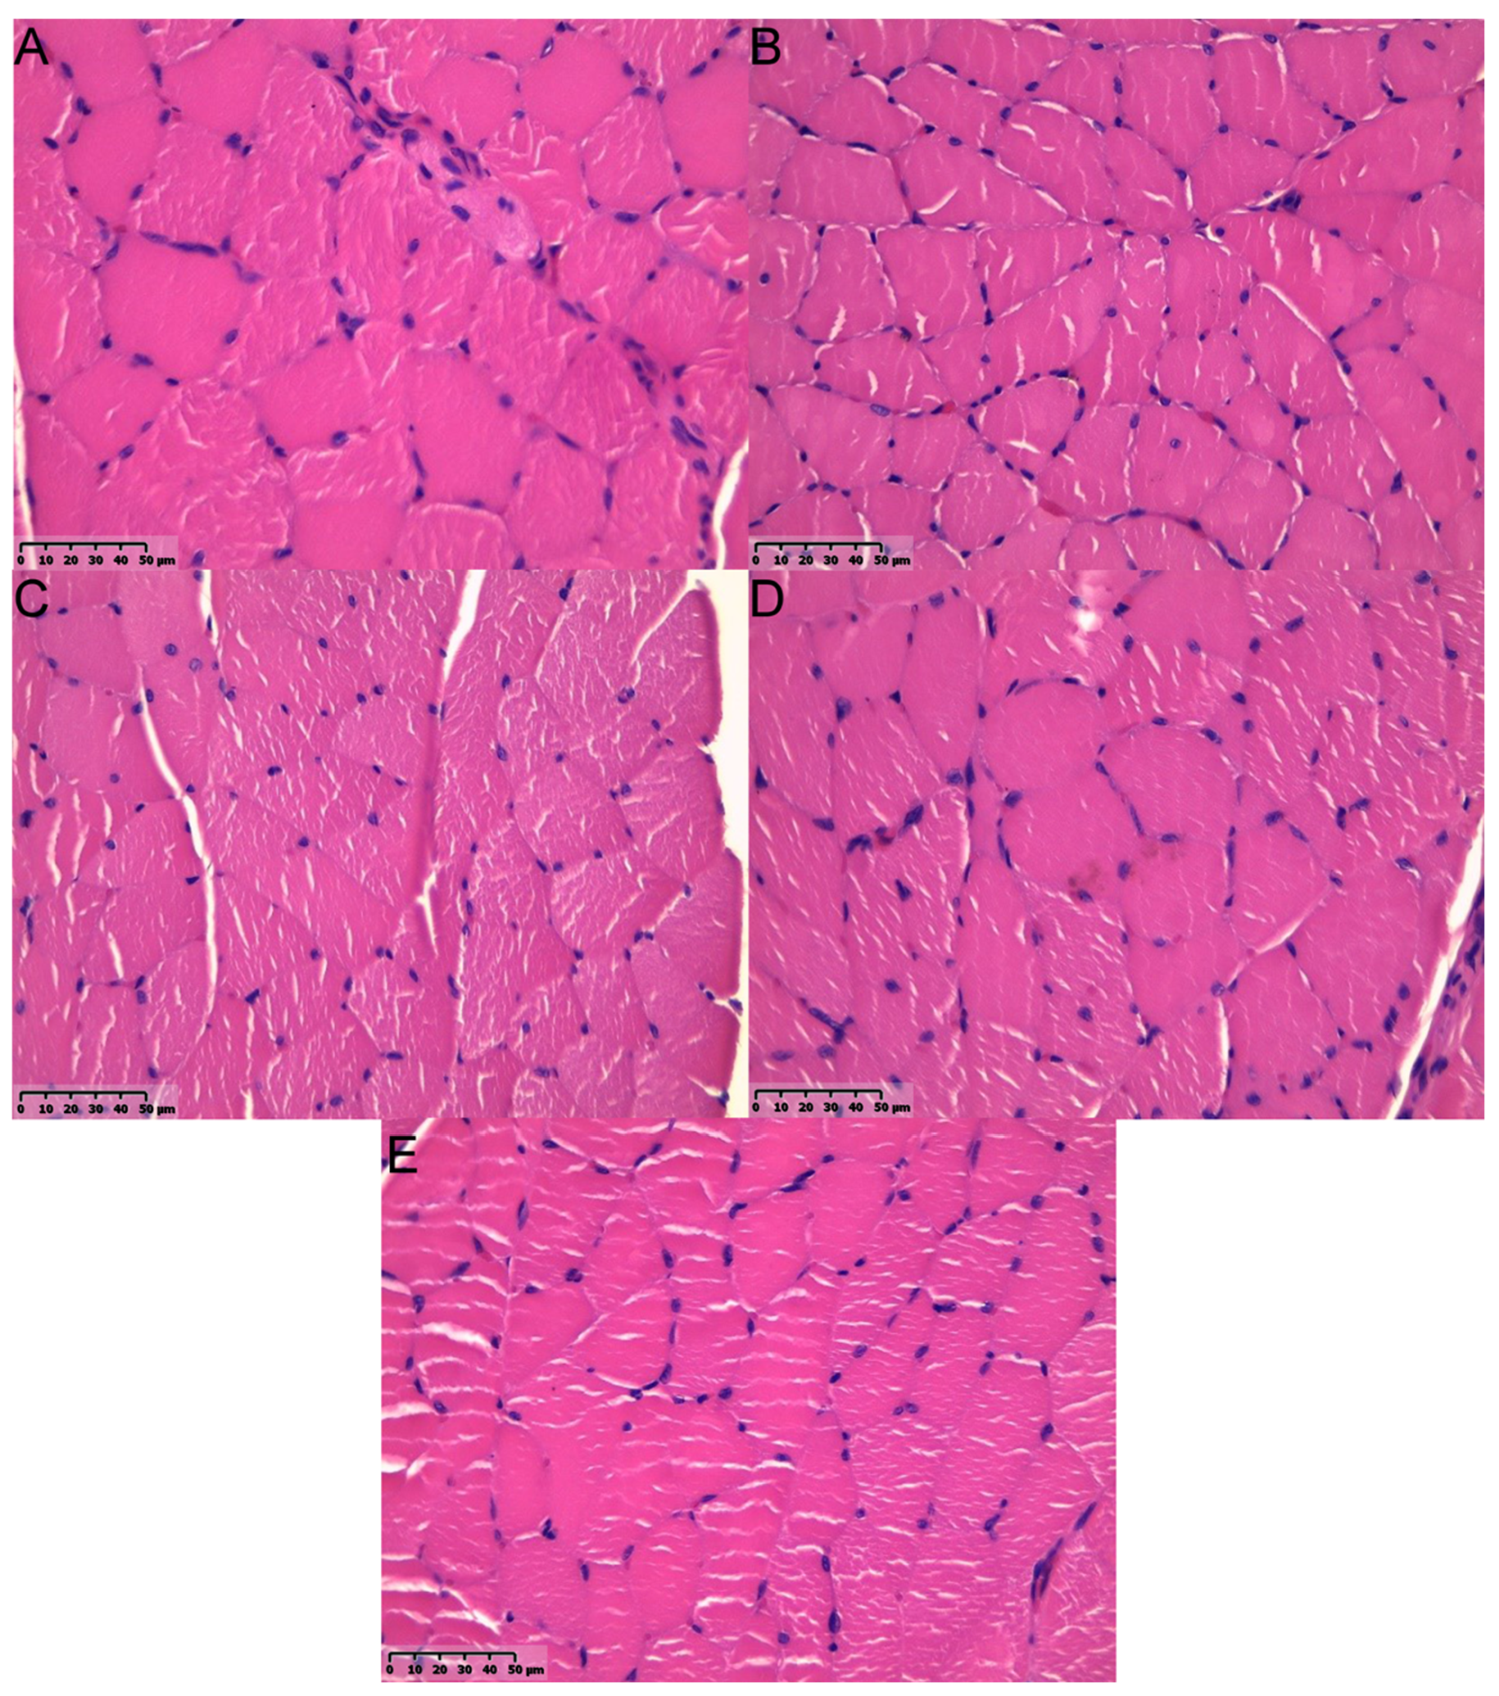

2.4. Muscular Tissue

Samples’ Harvest and Histological Analyses